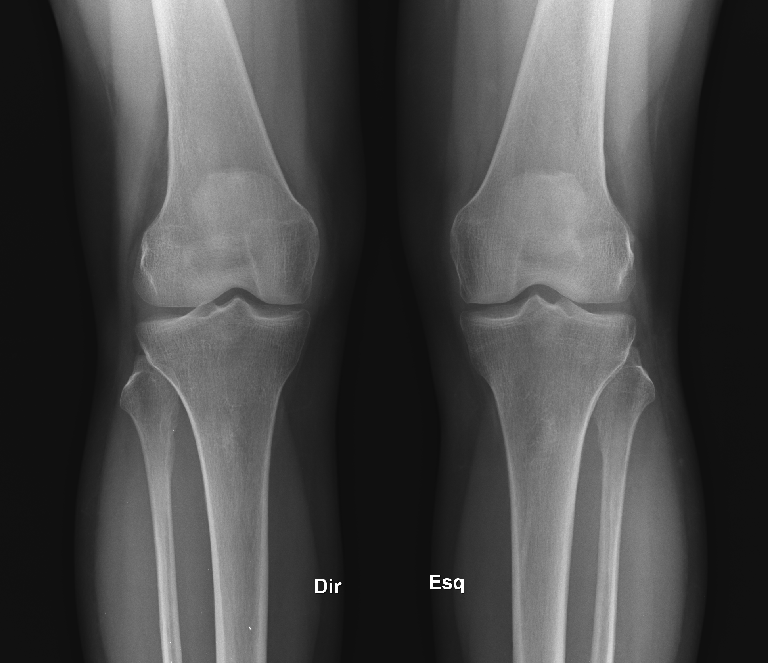

Normal Knee X Ray 13 Year Old . Citation, doi, disclosures and article data. It can show broken bones or a dislocated joint.

Web this is a repository of normal pediatric bone xrays and their examples for a quick reference look. Citation, doi, disclosures and article data. Normal appearances of the knee joint in the growing patient.

Normal appearances of the knee joint in the growing patient. Citation, doi, disclosures and article data. There mild or borderline patella alta. Education and training, education, plain radiographic studies, paediatric, musculoskeletal joint.

Normal Knee X Ray 13 Year Old - Normal appearances of the knee joint in the growing patient. Web this is a repository of normal pediatric bone xrays and their examples for a quick reference look. It can show broken bones or a dislocated joint. Web normal ap and lateral knee radiographs in an adult male for reference. This article lists examples of normal imaging of the pediatric.